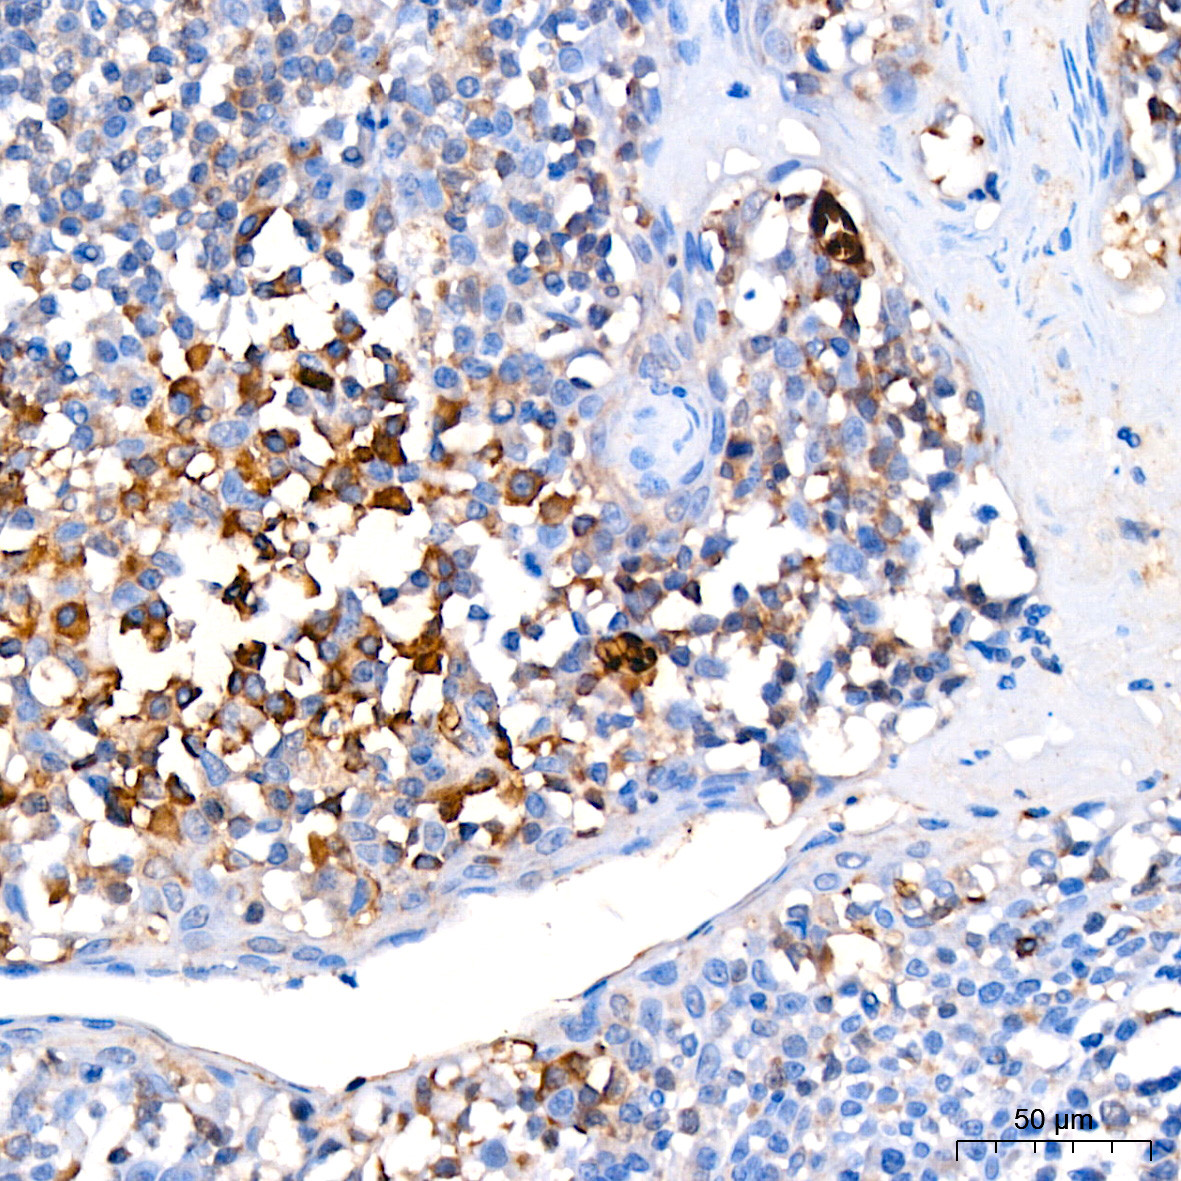

肿瘤血管生成(Tumor angiogenesis)是一个极其复杂的过程,一般包括血管内皮基质降解、内皮细胞移行、内皮细胞增殖、内皮细胞管道化分支形成血管环和形成新的基底膜等步骤。肿瘤血管生成的发生一方面是由于肿瘤细胞释放血管生成因子激活血管内皮细胞,促进内皮细胞的增殖和迁移,另外一方面也是因为内皮细胞旁分泌某些血管生长因子刺激肿瘤细胞的生长。在内部肿瘤团块缺氧环境下,缺氧诱导因子-1 (HIF-1) 的二聚蛋白复合体得以保持稳定,并激活众多导致血管生成过程的基因的表达。HIF-1诱导的蛋白包括血管内皮生长因子 (VEGF) 和碱性成纤维细胞生长因子 (bFGF)。血小板源性生长因子 (PDGF)、血管生成素-1 (ANG-1)、血管生成素-2 (ANG-2) 等其他分泌因子会促进趋化性,而肝配蛋白信号转导会控制迁移和细胞间黏附,从而引导新形成的血管。